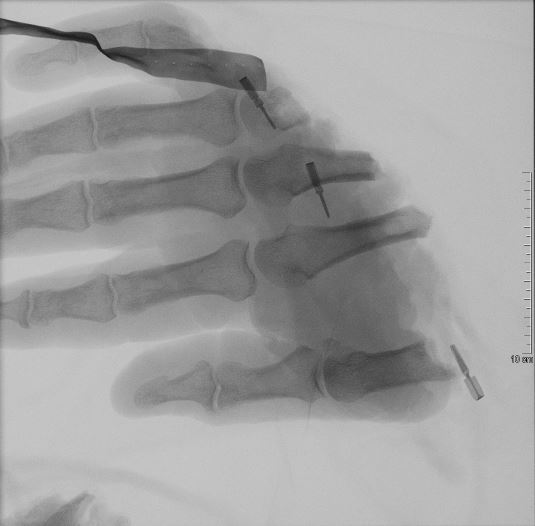

Das geröntgte Amputat. Bild: Sanitätsdienst der Bundeswehr Fotograf: Presse- und Informationszentrum des Sanitätsdienstes der Bundeswehr